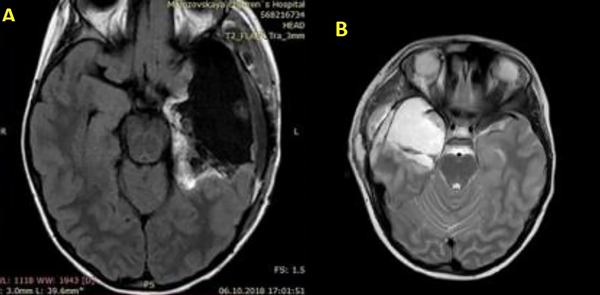

La amigdalohipocampectomía implica la eliminación del hipocampo, amígdala, uncus, giro parahipocampal y otras estructuras. No hay un método estandarizado para operar, pero las opciones incluyen lobectomía temporal anterior, amigdalohipocampectomía selectiva y amigdalohipocampectomía a través del giro temporal medio. Una craniotomía frontotemporal estándar comienza con una incisión en forma de signo de interrogación. Después de la apertura de la duramadre, se visualizan la cisura de Silvio, el giro temporal superior (T1) y el surco central. El primer paso en la amigdalohipocampectomía es penetrar al cuerno temporal del ventrículo lateral y eliminar el abultamiento del hipocampo en su superficie interna. El surco ventricular lateral es la entrada al giro parahipocampal, donde se realiza una resección subpial como primer paso quirúrgico (Figura 8). Luego, el hipocampo se puede mover lateralmente al espacio creado por la eliminación del giro parahipocampal para aspirar la fimbria de la piamadre subyacente. El hipocampo se elimina en un solo bloque. La resección anterior para lograr una amigdalohipocampectomía incluye la resección completa del uncus (Figura 5-7).23,24,25

Figura 5. Dos ejemplos de amigdalohipocampectomía postoperatoria con lobectomías temporales anteriores. A corresponde a un lado izquierdo y B a un lado derecho, una de las técnicas de tratamiento quirúrgico de la Epilepsia Refractaria a los Medicamentos.

Figura 6. Ejemplos de escaneos de RM postoperatorios después de la extracción de tumores, los cuales fueron la causa de convulsiones epilépticas resistentes a los medicamentos. A: corresponde a una cavidad quirúrgica del giro temporal medio derecho y B: a una cavidad temporal posterior izquierda.

Figura 7. Ejemplo de una amigdalohipocampectomía selectiva postoperatoria en un paciente con convulsiones persistentes. A y B muestran una vista sagital del enfoque, mientras que C y D desde la base.